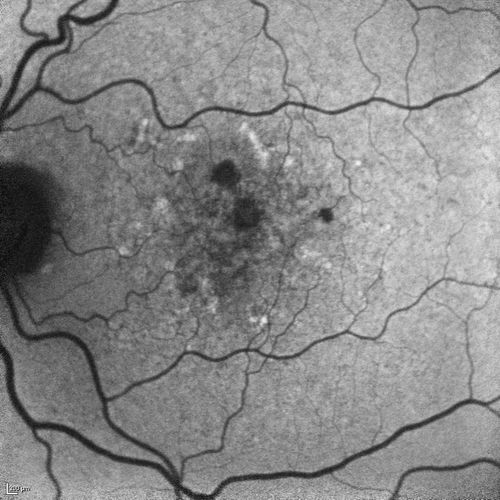

Dry AMD - Confluent Drusen Sparing Center of Macula which has Atrophy

65 year old woman, VA 20/40 OD; 20/80 OS. The center of the macula has few or no drusen with predominantly non-geographic atrophy